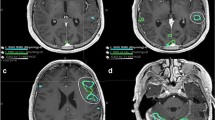

a Group-level contrast maps show areas that are differentially activated between different language tasks. Each contrast map represents results from a pairwise group-level analysis between the two listed tasks, thresholded at p-corrected ≤ 0.05 after TFCE. b Correlation between clinical scores and laterality indices computed at percentiles of subject activation for MR and VG tasks. Vertical red line highlights the percentile yielding the highest correlation (92nd percentile, corresponding to a correlation coefficient of 0.71). c For a representative subject with postoperative language deficits, the overlap (purple) is shown between the resection mask (blue) and the optimally thresholded language map (red). d A comparison of the overlap between the resection mask and the optimally-thresholded language map (y-axis) as a function of the volume of the resection mask (x-axis) is shown separately for patients with (red) and without (blue) postoperative language deficits. Overlap is shown separately for subjects with diagnoses of mass/AVM (filled triangle) or epilepsy (filled circle); the example subject shown in c is highlighted with a green circle. e Wada assessments are compared to LI results for laterality (left or right hemisphere). AL anterior-left brain orientation, AT auditory tones, PL passive listening, MR mental rhyming, VG verb generation, LI laterality index

Having demonstrated which tasks performed best in determining language laterality at the population level across a range of percentile-based thresholds, we asked whether a specific percentile threshold maximized the correlation between our results and the laterality assessments made at the time of original clinical testing and documented in each patient’s original radiology report. To do this, we first scored the laterality assessments from the original radiology reports (see “Methods”). Across all subjects, we then correlated the set of LIs computed at each percentile of subject activation with these clinical scores. Figure 3b shows that the correlation between LIs and clinical scores peaks at a percentile threshold of 92 (R = 0.71). At this threshold, the z-statistic for individual participants ranged from 4 to 10 (Online Resource 4). In contrast, when we used a fixed z-statistic of 4.5 to threshold each subject’s activation maps (as is the case for the BIP maps generated by BrainWave software), we found a much lower correlation between resulting LIs and clinical scores (R = 0.56).

As an additional validation of our optimal LI results, we compared the masked and thresholded language activations to postoperative language and imaging outcomes and also compared LI laterality results with laterality derived from preoperative Wada testing. When comparing subject-level language activations to postoperative outcomes, we found significantly greater overlap between resected regions and language activations in subjects with postoperative language deficits compared to those without (Fig. 3d). This difference was present in both our entire population (p = 0.019) and in the subset of 8 subjects with a primary diagnosis of mass/AVM (p = 0.040). Furthermore, for the small subgroup of 6 patients with results from preoperative Wada testing, the laterality determined from our optimized LI-based analysis was in complete agreement with laterality derived from the Wada assessment (Fig. 3e).